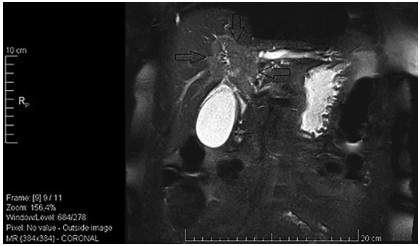

Abstract: Hilar cholangiocellular carcinoma (CCC) is a malignant neoplasm of epithelial origin occurring at the confluence of the right and left hepatic bile ducts. Typically, these tumors are small, poorly differentiated, exhibit aggressive biologic behavior with non-specific symptoms and tend to obstruct the intrahepatic bile ducts. Surgery is the only available curative option. Unfortunately, in less than half of the patients a complete resection is possible with poor survival rate in unresectable cases. In this report, we present the case of a 58-year-old woman with a history of unresectable hilar cholangiocarcinoma. Initially she was treated with intraductal dilatation of malignancy and placement of a plastic stent and chemotherapy (Gemcitabin® and Platinol®). Two years later she underwent a second-line chemotherapy with Gemcitabin® and Oxyplatin® because of tumor progression. Despite a second line chemotherapy and placement of an uncovered self-expandible metal stent (ucSEMS) that was extended later on by stent-in stent technique, there was tumor progression which led to a complex course with relapsing obstructive cholangiosepsis and cholestasis. Because of tumor ingrowth, endobiliary radiofrequency ablation of the malignant stenosis was performed in repeated sessions. This case illustrates that radiofrequency ablation of solitary malignant biliary obstruction is feasible, safe and allows an improvement of quality of life in non-operable patients.